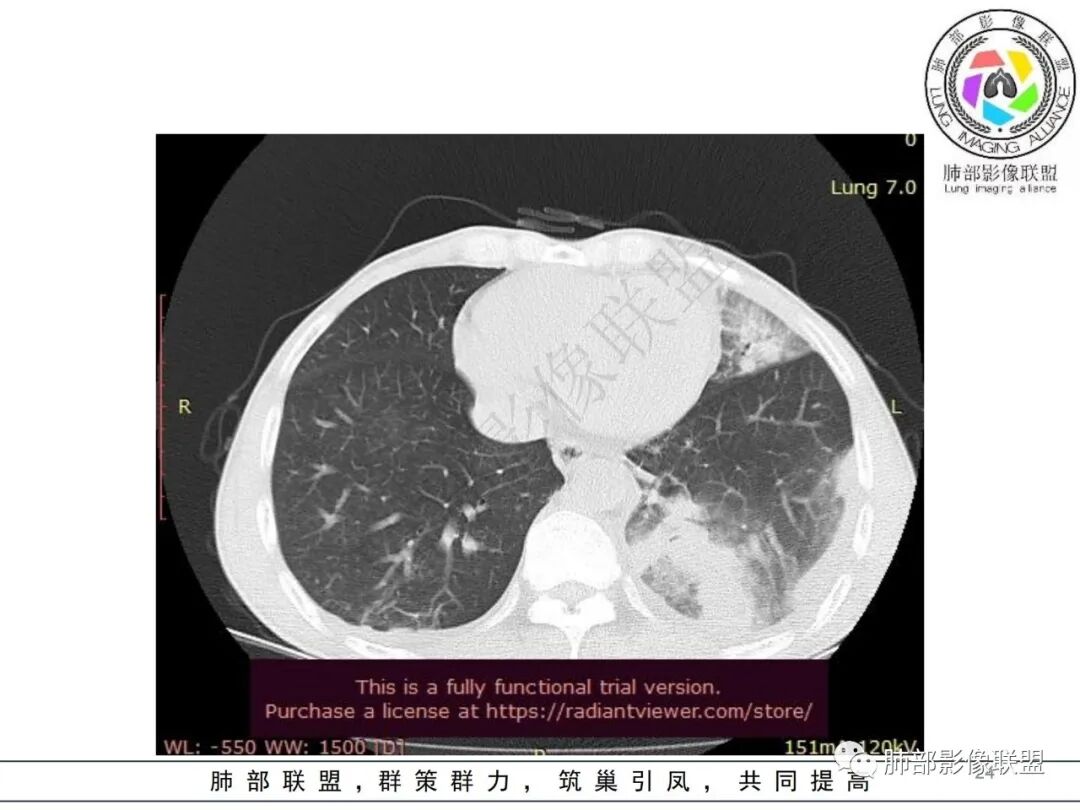

影像表现:双肺弥漫分布斑片影、实变影、磨玻璃影、结节影,晕征、反晕征,随机分布,部分病灶空洞形成前兆,左侧胸腔积液。

但是肺克肝脓肿血播到肺的,看过很多,没有类似晨读那样表现的,今天晨读不是太典型的血播影像表现;复查的影像就很典型

觉得后面那些符合血道,左下的更符合气道的

目前大家支持的观点:肠道来源,肺血播,累及气道

常规分析:左侧胸水,左下肺病灶大,周围渗出明显,气道壁增厚,内部还无坏死,复查坏死空洞也小

影像表现:双肺多发结节、实变影,大部分病灶边界不清,随机分布趋势,左下肺“反晕征”,似有形成空洞趋势。左侧胸腔积液。治疗后复查 ,大部分病灶吸收好转,呈较为典型血播分布,肝脏低密度块影,边界不清,符合肝脓肿。